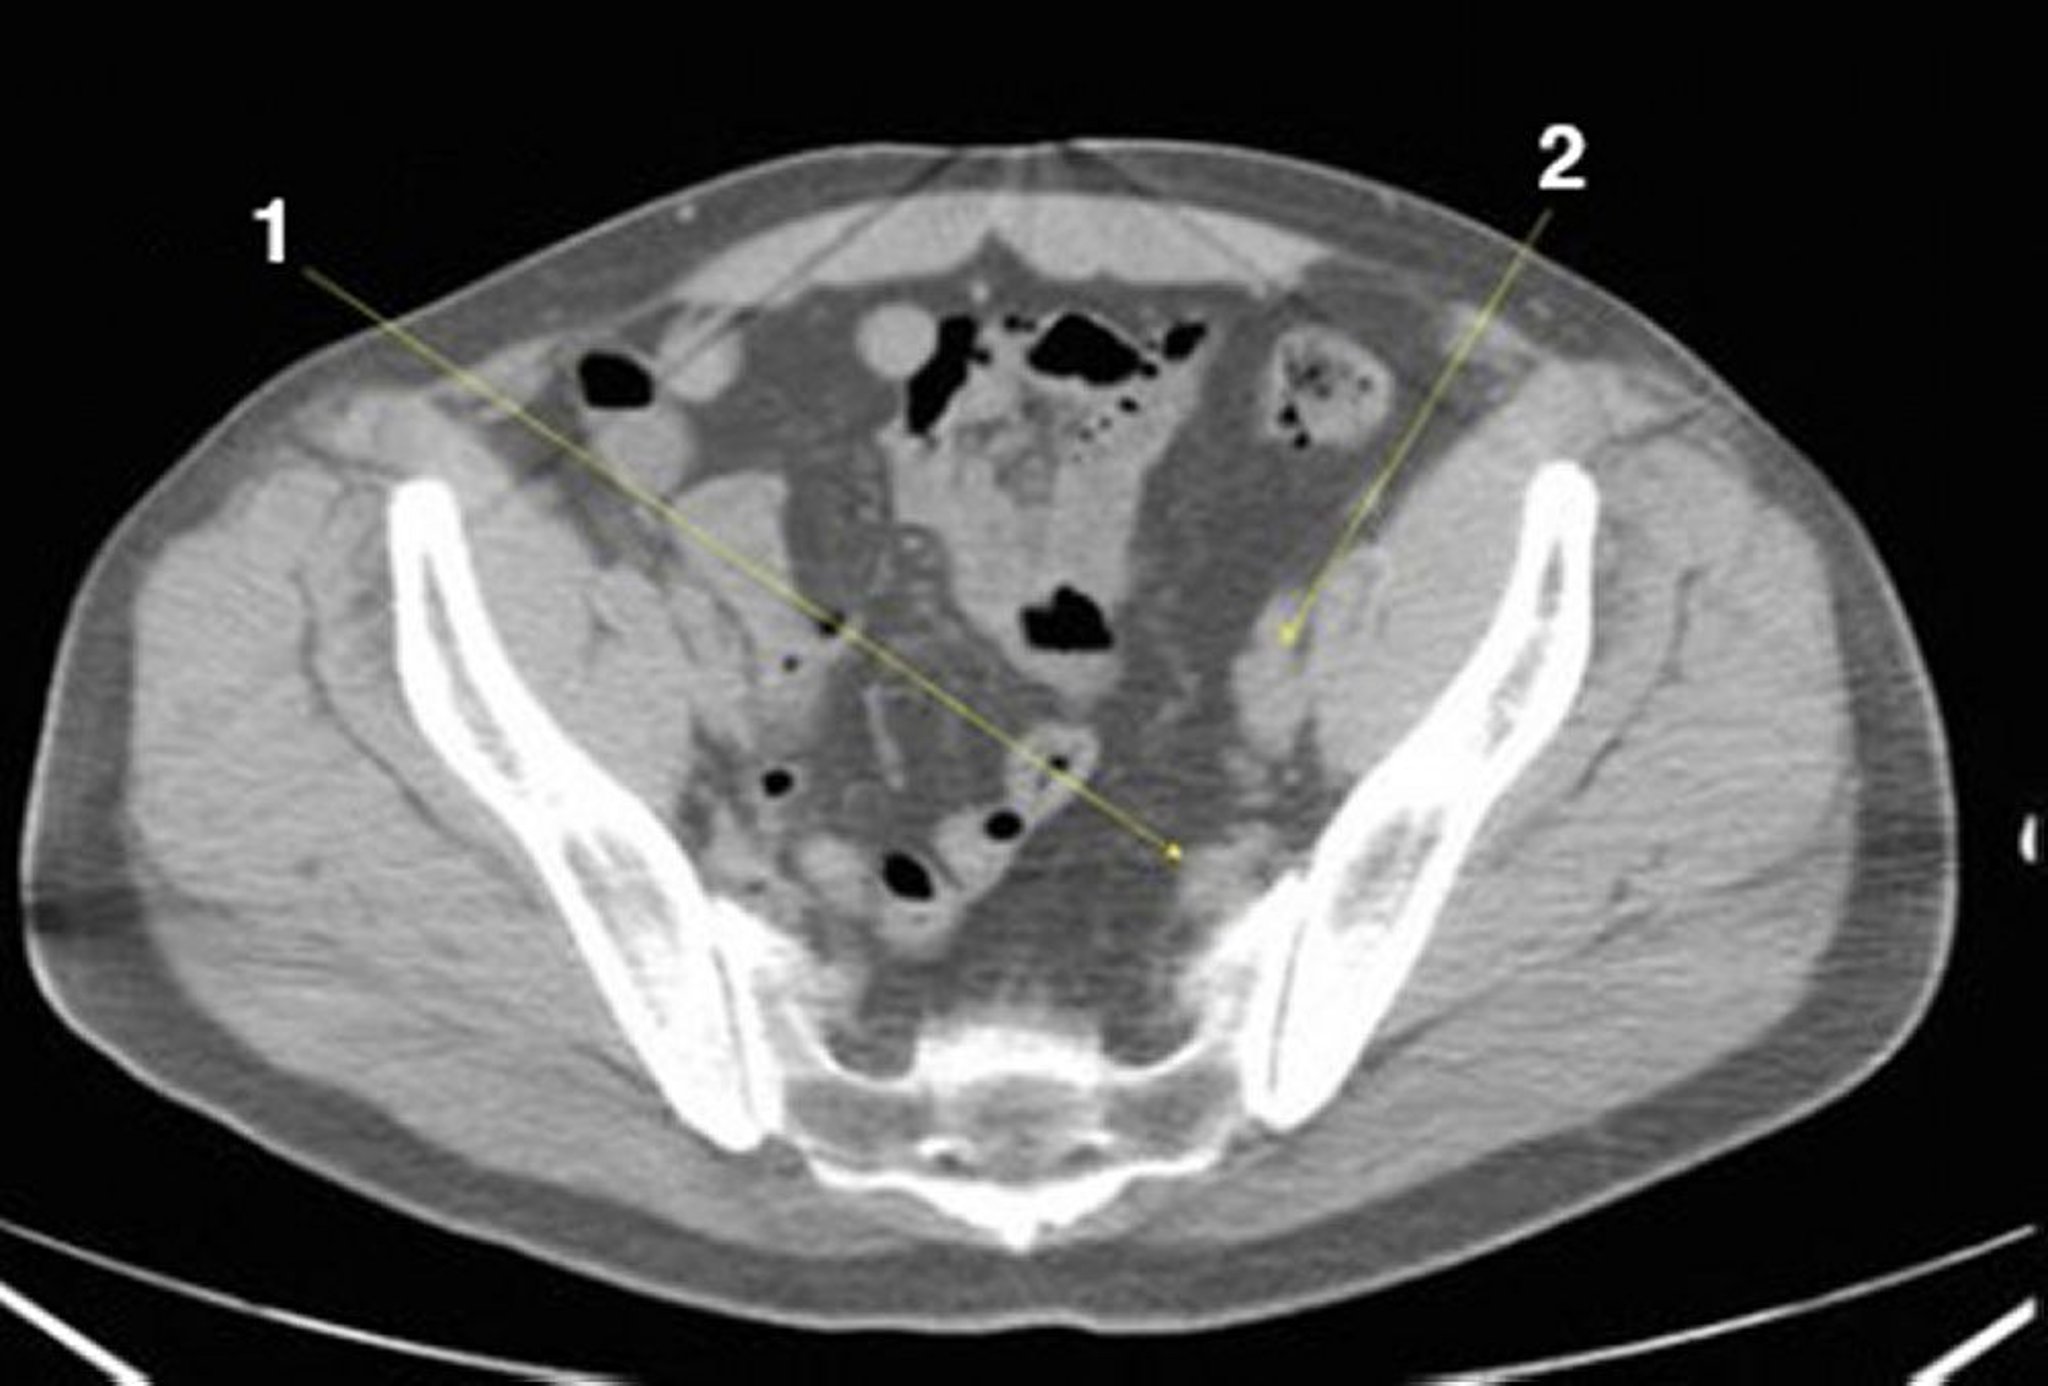

TC sem contraste do abdome e da pelve mostrando anatomia normal (lâmina 24)

1 = vasos ilíacos internos; 2 = vasos ilíacos externos.